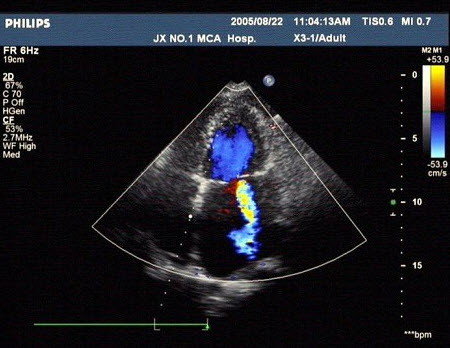

41、单项选择题

某患者肝脏发现肿块回声,根据CDFI声像图表现,最可能的诊断是()